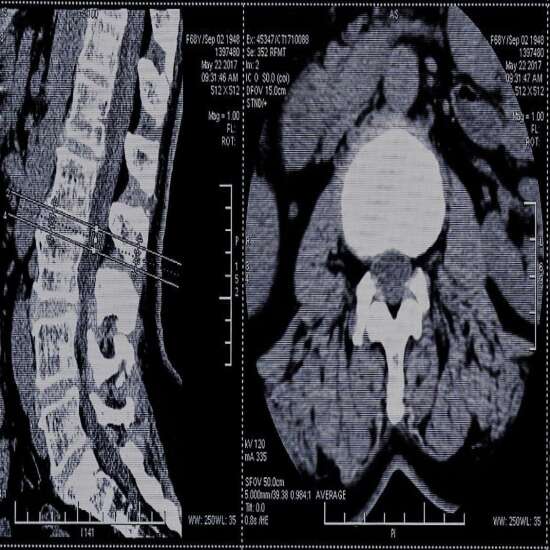

CECT LS Spine - Test, Cost & Procedure

CECT Lumbar Spine

CECT Lumbar Spine is a contrast study in which dye is used to diagnose spinal injury.

CECT lumbar spine scans are the Contrast-Enhanced Computed Tomography scan of the lumbar spinal region.